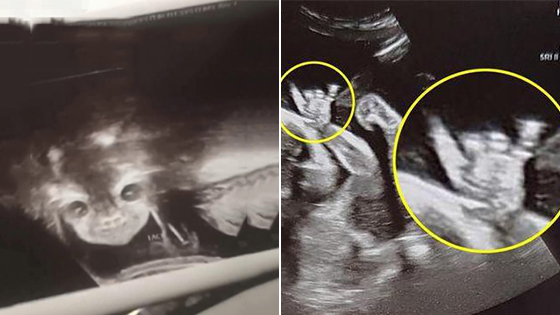

检查时,护士将仪器贴在她的肚子上,一边和她聊天一边扫描。护士告诉她孩子发育得很好,是个漂亮的宝宝。在护士建议下,她准备看看自己肚子里的孩子。然而,当她看向屏幕时,腹中宝宝似乎有感应, 突然睁开了双眼,还露出了奇怪的笑容。屏幕是黑白的,当时的影像更像婴儿主题恐怖电影。

伊安娜被这一幕吓坏了,到医生办公室询问为什么自己的宝宝这么可怕,医生笑着告诉她真相>>